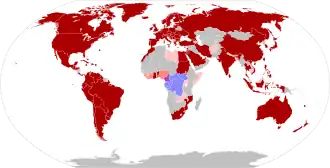

Mpox is endemic in central and western Africa, where several species of mammals are suspected to act as a natural reservoir of the virus.[1] The first human cases were diagnosed in 1970 in Basankusu, Democratic Republic of the Congo.[13] Since then the frequency and severity of outbreaks has significantly increased, possibly as a result of waning immunity since the cessation of routine smallpox vaccination.[13] The 2022–2023 mpox outbreak represents the first incidence of widespread community transmission outside of Africa. This was initially identified in the United Kingdom in May 2022, with subsequent cases confirmed in 111 countries as of May 2023.[14] The World Health Organization (WHO) declared the outbreak a Public Health Emergency of International Concern (PHEIC) between 23 July 2022 and 10 May 2023.[15]

This section is an incomplete list of disease outbreaks which have been reported outside the endemic countries in tropical Africa (Benin, Cameroon, the Central African Republic, the Democratic Republic of the Congo, Gabon, Ghana, Ivory Coast, Liberia, Nigeria, the Republic of the Congo, Sierra Leone, and South Sudan).[54] Outbreaks of mpox are frequent in areas where the disease is endemic - these areas often have poor healthcare infrastructure and outbreaks are rarely documented.[55][56][57]

2022–2023 Global outbreak

An outbreak of mpox was confirmed in May 2022.[70] The initial cluster of cases was found in the United Kingdom,[71] where the first case was detected in London on 6 May 2022[72] in a patient with a recent travel history from Nigeria (where the disease is endemic).[73] On 16 May, the UK Health Security Agency (UKHSA) confirmed four new cases with no link to travel to a country where mpox is endemic. All four cases appeared to have been infected in London.[72] From 18 May onwards, cases were reported from an increasing number of countries and regions, predominantly in Europe and in the Americas but also in Asia, in Africa, and in Oceania.[80] In May 2023, the World Health Organization declared an end to the global health emergency declared in response to the worldwide outbreak of mpox virus.[81]